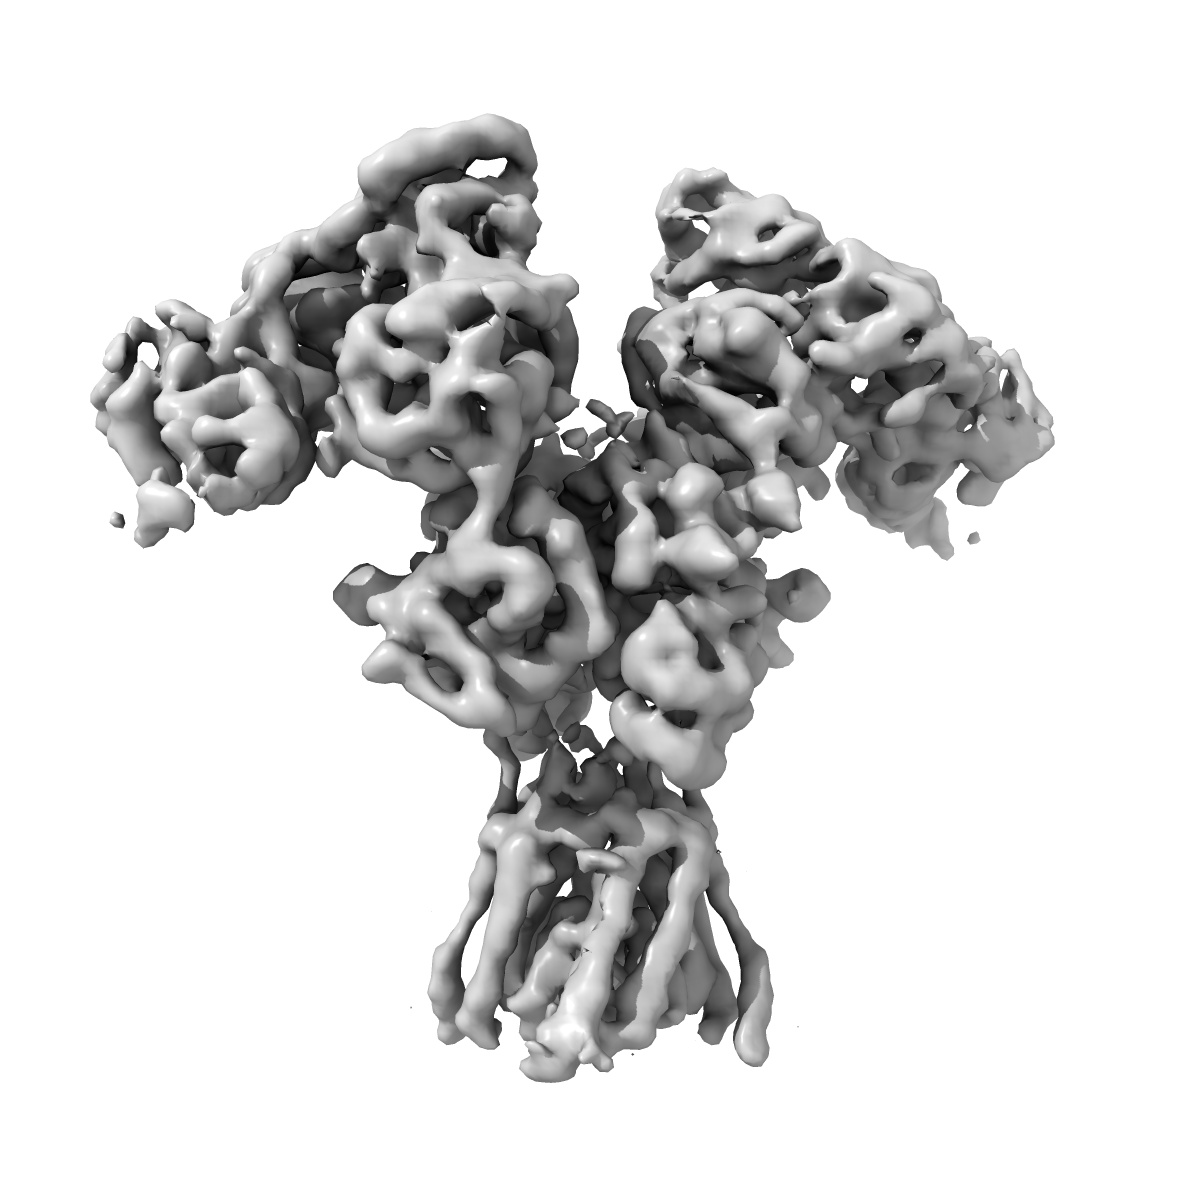

Cryo-EM structure of GluN1b-2B NMDAR in complex with Fab5 in non-active2-like conformation

Sample: GluN1b-2B NMDAR complexed to Fab5

Fitted models: 7tet

Development and characterization of functional antibodies targeting NMDA receptors.

Tajima N, Simorowski N, Yovanno RA , Regan MC, Michalski K, Gomez R , Lau AY , Furukawa H

(2022) Nat Commun , 13 , 923 - 923